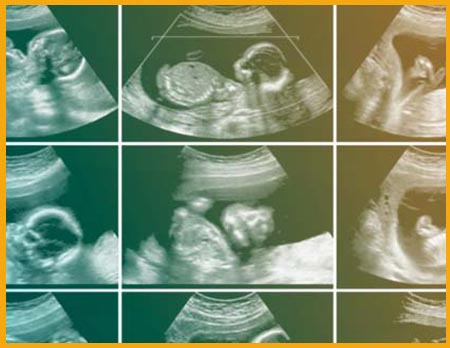

اسکن آنومالی که سونوگرافی اواسط بارداری یا سونوگرافی تفضیلی نیز نامیده میشود بین هفته های ۱۵تا ۲۸ قابل انجام است. اما از انجا که براساس قوانین ایران ، سقط درمانی با محاسبه ی تاریخ اولین روز قاعدگی فقط تا پایان هفته ی ۱۹ امکان پذیر است ، این اسکن در فاصله ی هفته های ۱۶-۱۸ بارداری انجام میشود تا در صورت وجود مشکلی که نیاز به ختم بارداری دارد ، این امکان برای والدین وجود داشته باشد. در این مطلب میتوانید با موارد قابل بررسی در اسکن انومالی برای زنان باردار و اقدامات لازم در صورت تشخیص احتمالی آشنا شوید.

در این سونوگرافی ، متخصص یک بررسی بسیار دقیق از اندام جنین و رحم شما انجام میدهد و رشد طبیعی جنین و محل قرار گیری جفت در رحم را بررسی میکند. فراموش نکنید که احتمال بروز ناهنجاریها تنها در ۵ در صد جنین ها اتفاق می افتد، بنابراین انجام اسکن ناهنجاریهای جنینی نباید موجب نگرانی شما شود. همچنین پزشک در این اسکن میتواند جنسیت نوزاد را به دقت تعیین کند.اندام های مختلف جنین که در اسکن آنومالی مورد بررسی قرار می گیرد ، شامل موارد زیر است :